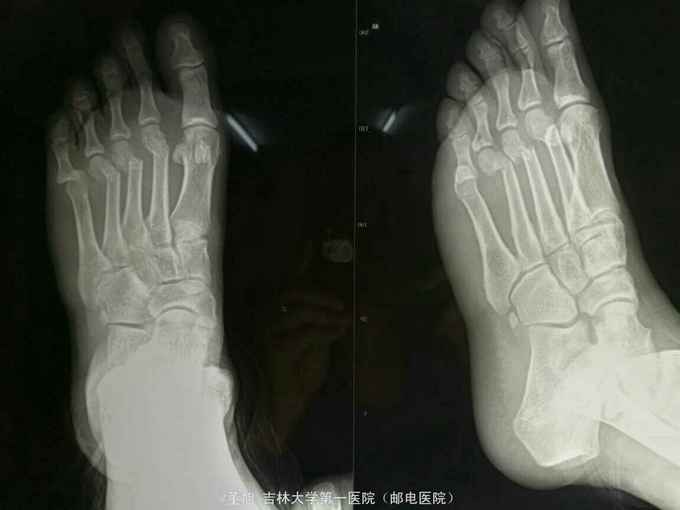

主诉:外伤后左足部肿胀,疼痛,活动受限3小时 现病史:患者自述于3小时前不慎从高处摔落,伤后出现左足部疼痛症状,不能站起行走,无足部麻木,自述未伤及头部,未行任何治疗,现为求明确诊治来我院,经查体拍片后以足部骨折收入院。患者自入院以来精神状态良好,未进食水,未排二便

查体:左足皮肤无破损,远端畸形,足背软组织肿胀,皮下淤斑,第二三四跖骨远端压痛,可触及骨擦感及异常活动,足趾活动受限,肢端感觉及血运良好 辅助检查:左足第二三四跖骨颈骨质连续性中段

诊断:左足第二三四跖骨粉碎骨折 左足背软组织挫伤 治疗:切开复位克氏针固定术